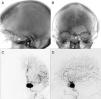

MethodsA total of six patients were treated: four patients with five aneurysms, one patient with an MCA stroke, and one patient with a meningioma requiring preoperative embolization were initially thought not to be amenable to endovascular treatment. The decision was made to treat these patients with transcirculation approaches. All patients were treated by one interventionist. One aneurysm was located in the cavernous internal carotid artery (ICA), one in the vertebral artery, two in the paraclinoid ICA, and one in a cerebellar AVM feeder vessel were treated.

ResultsFive of six patients (83%) made a full neurologic recovery. Three aneurysms were treated to complete occlusion, one aneurysm was left with small residual neck filling, and one aneurysm was not able to be treated. One patient underwent mechanical thrombectomy of a middle cerebral artery (MCA) embolus and MCA filling was restored after treatment. One patient underwent complete embolization of the deep vascular supply of a meningioma.